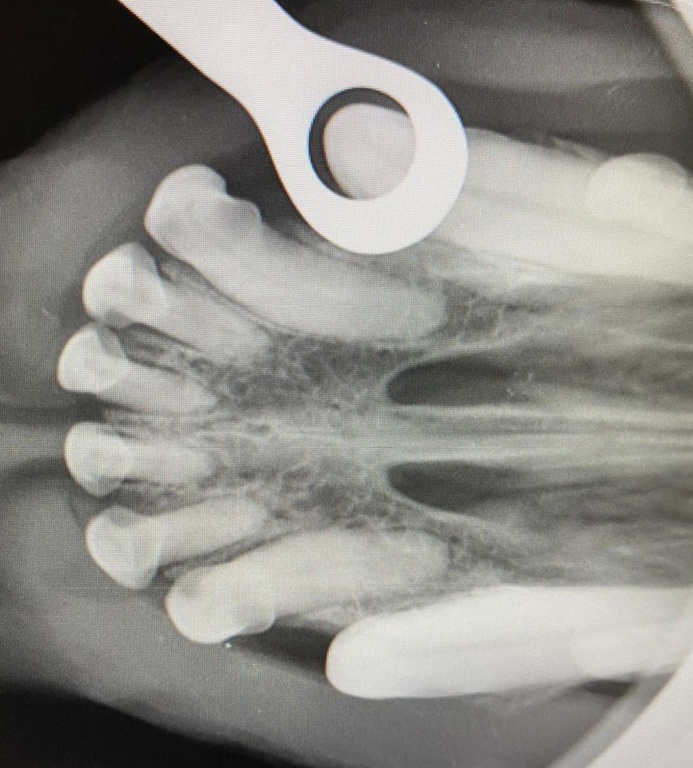

Röntgen

Mit unserer modernen digitalen Röntgenanlage können wir sicher und zuverlässig die Verletzung Ihres Tieres schnell und unkompliziert erkennen. Im Vergleich zum analogen Röntgen kann man mit der Lupenfunktion bestimmte Bereiche noch genauer anschauen. Durch digitales Röntgen kann man mit einer eventuellen Bildnachbearbeitung dem Tier eine zusätzliche Röntgenbestrahlung ersparen.